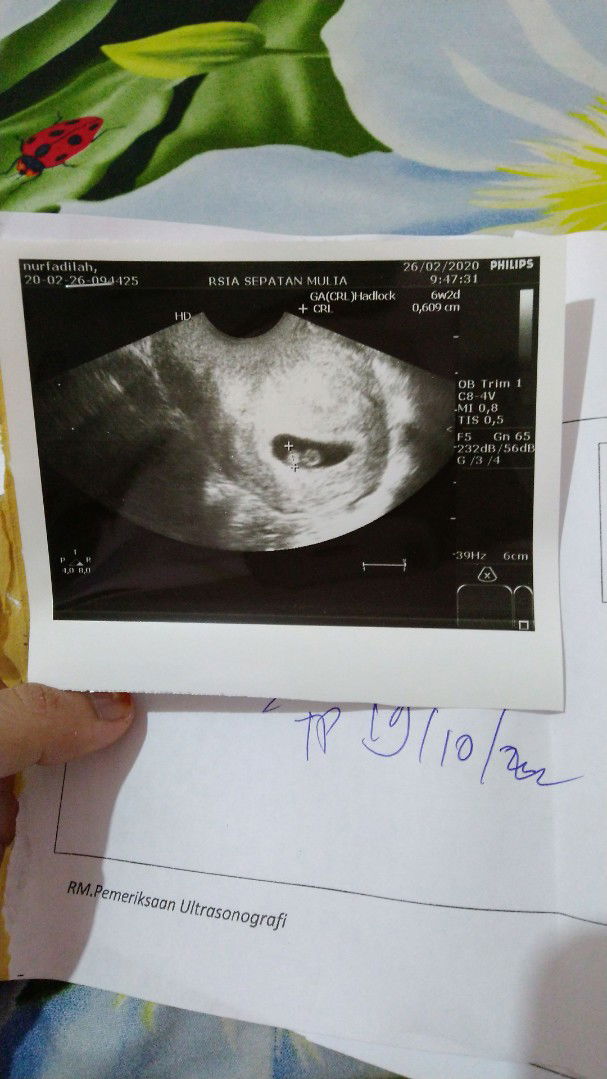

ini usg bayi kembar apa bukan?

Bun mau tanya, ini aku usg pas kandungan usia 6 minggu. Ipar sm mama ku bingung knapa ada 2 buletan nya. Tp dokter nya ga bilang apa2. Itu kembar atau engga ya bun? Dan yg berdenyut jantungnya cuma 1. Jd yg sebelahnya itu apa ya bun?